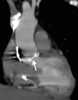

Aortic aneurysm

Arterial aneurysm

Renal artery aneurysm or microaneurysm